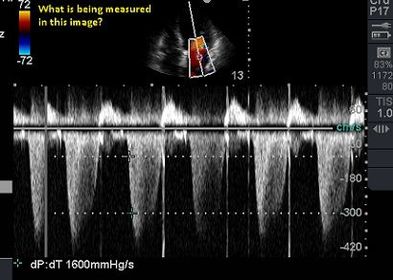

Left Ventricular systolic performance, or ventricular contractility assessment |

| In the DP/DT formula, what is being measured? | The increase in pressure divided by the time interval necessary for that increase to occur |

| How is the DP number obtained? |

| Normal dp/dt values? | >1200 mmHg/sec |

| Borderline dp/dt values? | 1000-1200 mmHg/sec |

| Abnormal dp/dt values? | < 1000 mmHg/sec |